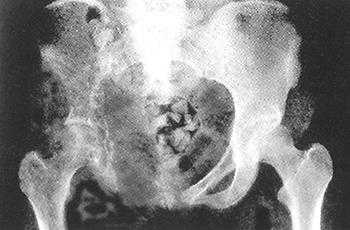

Необъяснимым до сих пор остается тот факт, что, имея достаточно агрессивное течение, болезнь Горхема может непредсказуемо переходить на стадию регресса. Но, к сожалению, в большинстве случаев прогноз на выздоровление неблагоприятный. Диагностируют синдром с помощью рентгенологического исследования, во время которого и определяются рассосавшиеся участки кости, где образуются дефекты, видные на снимке. Это так называемые литические очаги, в некоторых случаях сочетающиеся со склерозом костной ткани.

Диагностика патологии очень простая. Результаты обследования видны при проведении рентгенографии. При этом на пленке четко выделяются области разрушения костей и степень их повреждения. На основании этого варианта проверки врач делает заключение.

Рентгенографию назначают и в начале развития болезни, это очень положительный диагностический фактор. Если диагноз необходимо подтвердить, то тогда потребуется более глубокое обследование - МРТ сканирование.

Радиологические находки.

Рентгенография и КТ

Интрамедуллярные или субкортикальные очаги часто являются первым проявлением патологии

Патология прогрессирует до глубокого остеолизиса пораженной кости без компенсаторных механизмов.

Один из симптомов заболевания — это упомянутый выше остеолиз, то есть полное рассасывание некоторых костных тканей, которые ничем не замещаются. Также происходит фиброз (разрастание соединительной ткани). На рентгеновском снимке всегда видны подобные видоизменения: кость кажется частично, а иногда и полностью усеченной, или даже ампутированной. Также существенные изменения можно обнаружить и на границе с очагом остеолиза (конец кости будто отшлифован, закруглен или заострен).